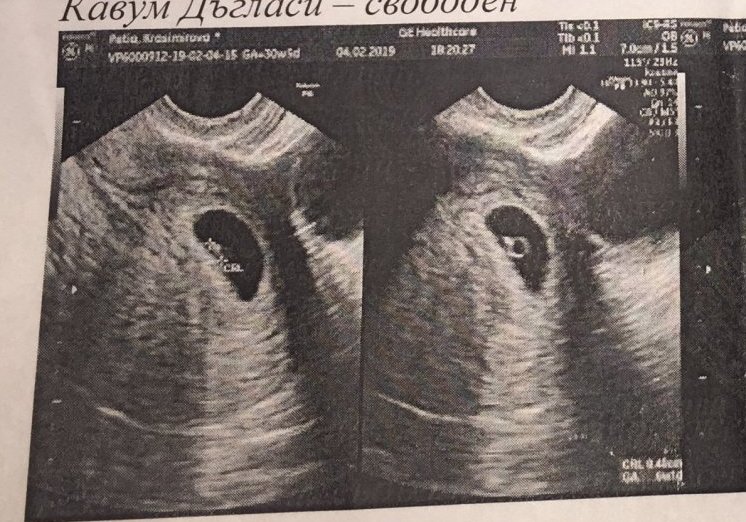

Здравейте, момичета! Скоро писах за притеснението от спрелите болки в гърдите. Днес посетих гинеколога си заради това и ето резултата. Какво мислите, нещата нармално ли се развиват спрямо седмиците (6 г. с.)? Каза ми, че имам жив ембрион 4 мм. със сърдечна дейност, както и, че кистите няма да навредят на бременността.

В 6г.с жив ембрион със сърдечна дейност е това, което трябва да се вижда. Но все пак ние не сме лекари. Тъй че слушай си доктора и спокойна бременност. Simple Smile